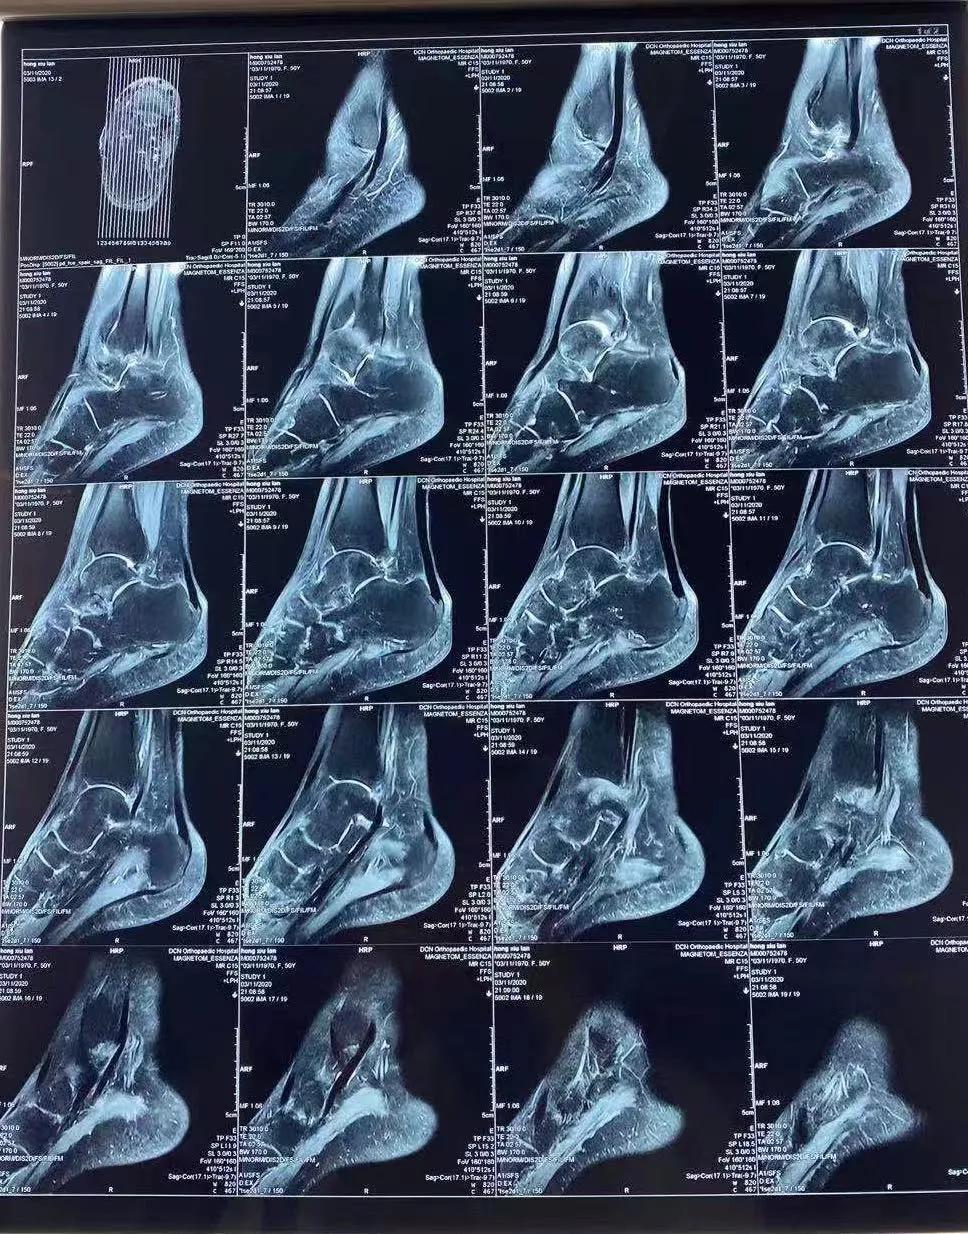

实例:洪女士,50岁,扭伤后,自行石膏固定,由于疼痛长期卧床一动不动,伤后3-4个月,症状没有缓解,当地治疗效果不佳,来我院行康复治疗。影像学检查后发现挫伤严重,肿胀,血供差,局部皮肤颜色加深,并伴有骨质疏松症。